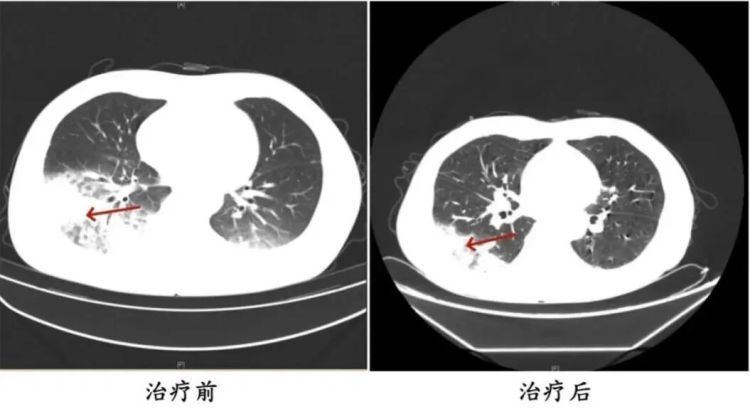

呼吸内科主任沈三英详细询问,并为患者完善了相应检查。结果显示,张先生的左肺竟然“白”了一大片。气管镜检查后,团队再通过肺泡灌洗液NGS检测抓住元凶——军团菌。

所幸张先生就医及时,目前体温恢复正常并已顺利出院。